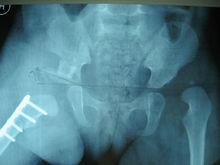

3. 18月齡到8歲患兒

大於18月齡的DDH患兒髖臼發育潛力很差,在做髖關節切開復位的同時多數需要做骨盆截骨術,4歲內的DDH患兒可以選擇Salter、Pemberton、Dega等骨盆截骨,對於脫位高、復位後關節壓力大、前傾角和頸乾角大的患兒需要同時做股骨近端的短縮、去鏇轉和內翻截骨。對於大於4歲的患兒在做上述手術同時,對於手術後再次脫位等複雜情況,也可以進行骨盆三聯截骨手術。具體手術方式的選擇,醫生需要根據髖關節的病理改變、患兒年齡等因素來決定。

發育性髖關節發育不良雙側髖關節脫位

發育性髖關節發育不良右髖切開復位、Pemberton骨盆截骨、股骨近端短縮去鏇轉截骨術後

發育性髖關節發育不良右側術後8個月